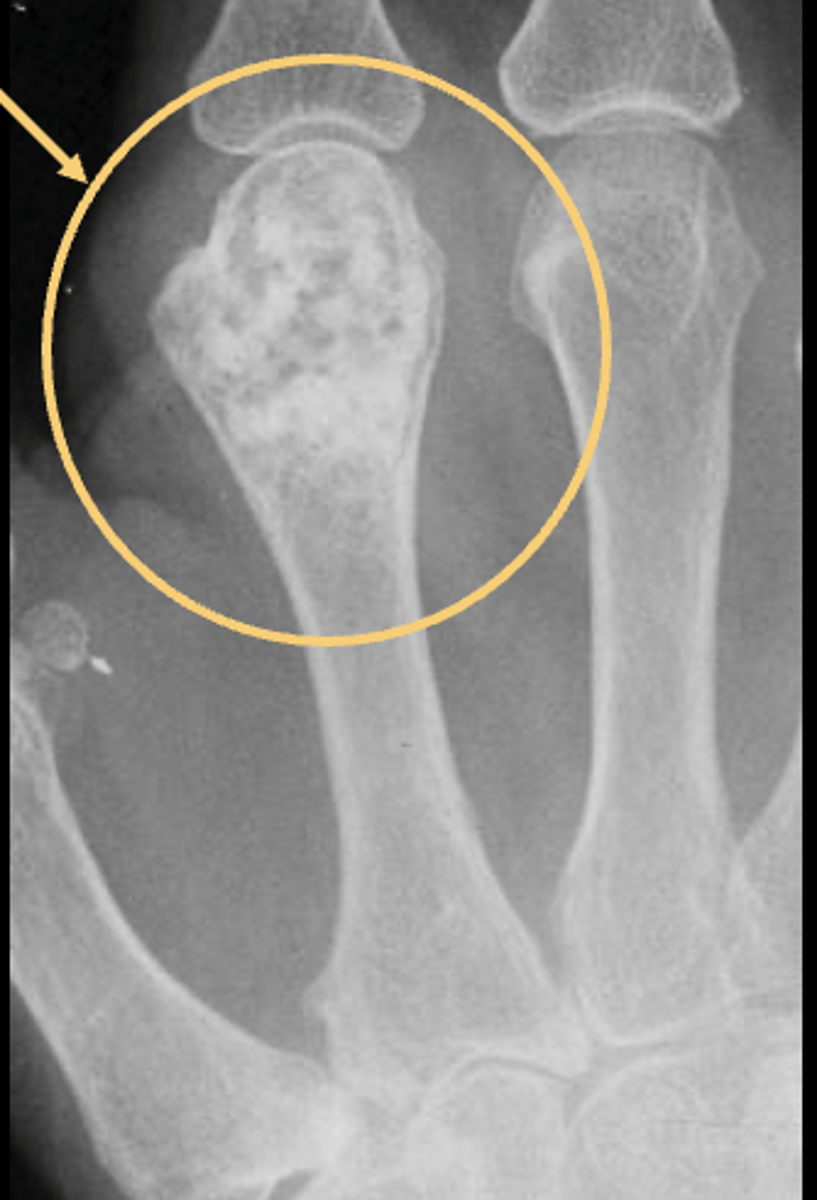

49

New cards

Matrix calcification

ID feature of solitary enchondroma

<p>ID feature of solitary enchondroma</p>

50

Endosteal scalloping

51

Multiple enchondromas

ID benign tumor

<p>ID benign tumor</p>